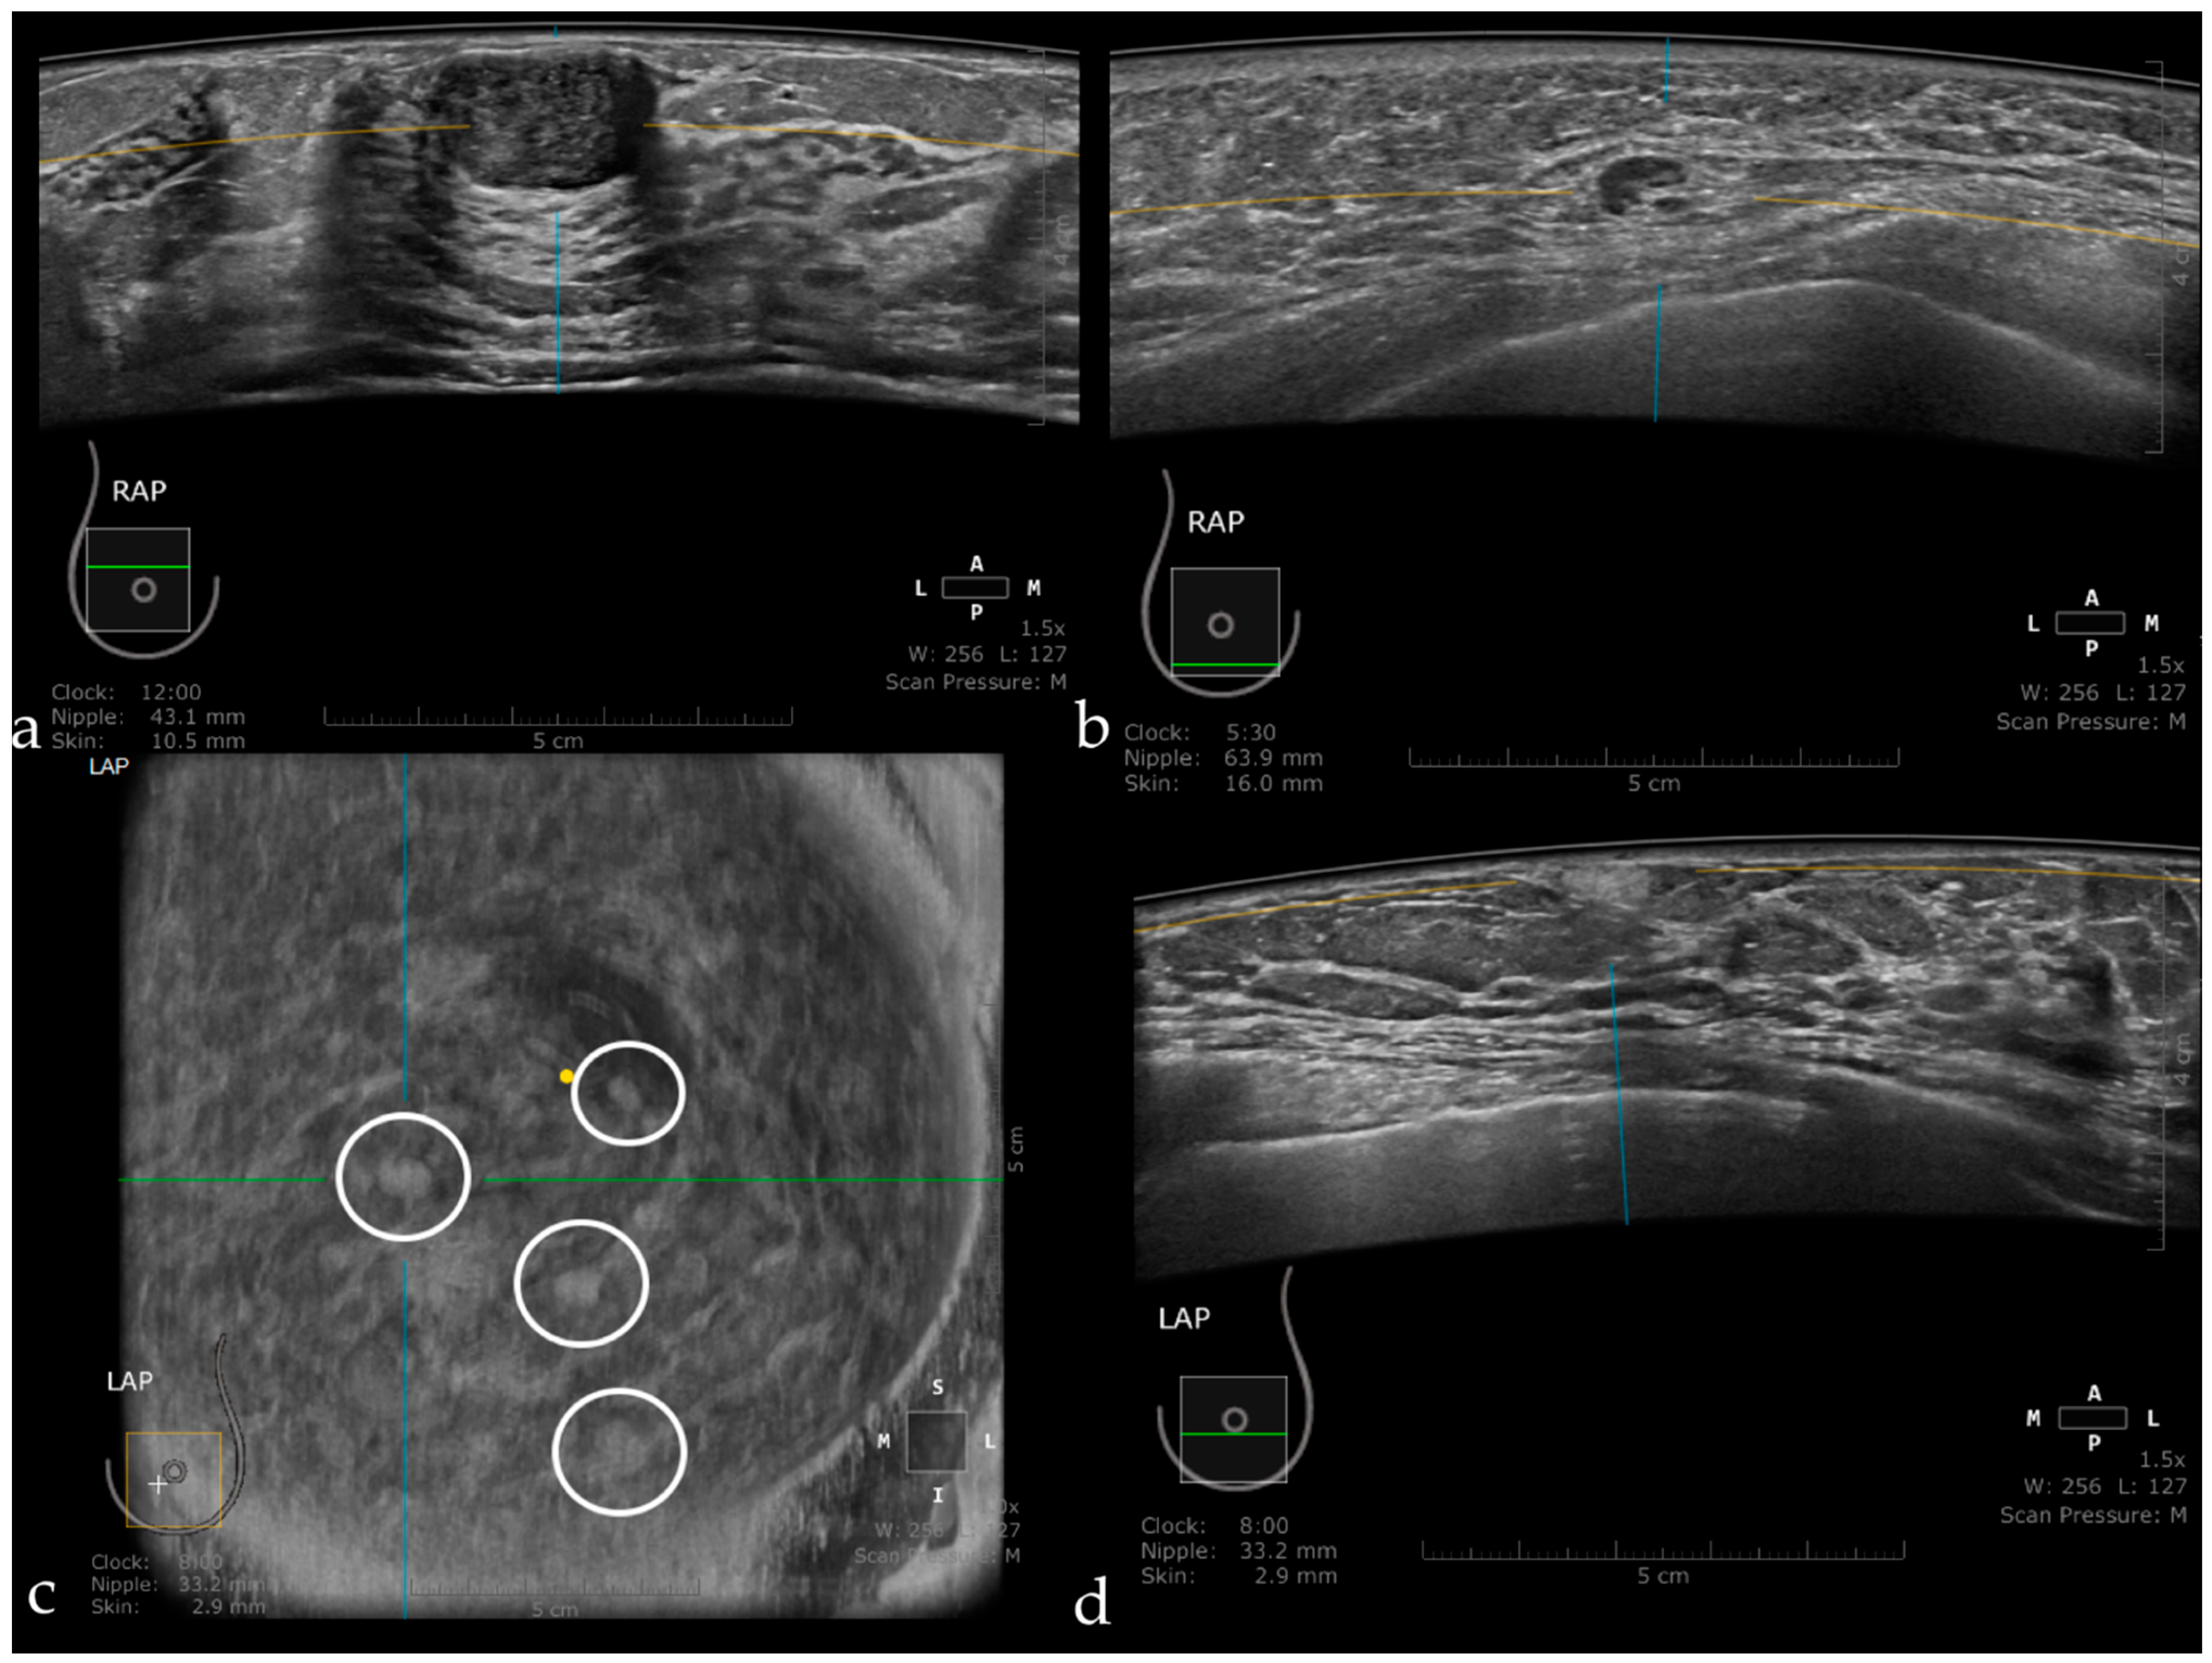

The Usefulness of the Coronal Plane

3.1. Technique and Artifacts

3.1.1. Limitations Related to the Technique

3.1.2. Artifacts

Artifacts Induced by the Use of Ultrasound Gel

Air Interposition

Insufficient Compression

Probe Motion Artifacts

Breathing Artifacts

Skip Artifact

Nipple Artifact

Attenuation Areas

White Wall Sign